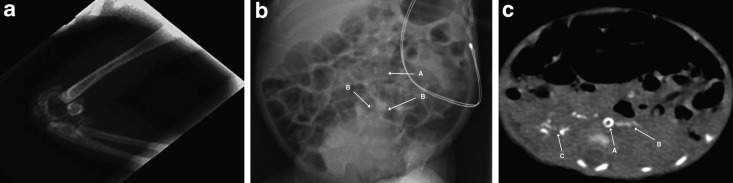

The patient was the second child of consanguineous Moroccan parents. The mother is a 40-year-old woman, who had seven previous pregnancies: a 16-year-old healthy boy, two miscarriages, two voluntary interruptions, and two stillborn infants delivered at 28 and 30 weeks of gestation. Amniocentesis of the current pregnancy revealed a normal 46, XY karyotype. In the 28th week of gestation, maternal hypertension was detected and fetal ultrasound outlined a severe pulmonary stenosis, tricuspid regurgitation (TR), cardiomegaly, polyhydramnios, and poor fetal movements. The mother underwent an urgent cesarean section because of acute fetal distress. The infant had a birth weight of 1,094 g, APGAR score was 4/6/10 at 1, 5 and 10 min, respectively, and the baby was intubated and ventilated. Physical examination showed no dysmorphic features, a grade 1 systolic murmur, a heart rate of 165 bpm and poor peripheral pulses. The liver was palpable 0.5 cm below the lower costal margin. The arterial blood pressure was normal (48/23 mmHg). Echocardiography, performed on the first day of life, revealed poor ventricular function (ejection fraction 40%), severe left ventricular hypokinesia and hypertrophy, brightness and hyperreflexia of the aortic wall from the arch to the abdominal tract with a low abdominal aorta pulsatility index. Inotropic support was immediately started with dobutamine and dopamine. Laboratory evaluation on the first day of life revealed elevated inflammatory markers (leukocytes 26,2100/μl [5,000–21,000/μl]); CrP 5.97 mg/dl [<0.5 mg/dl]; platelets 32,000/μl [250,000–450,000/μl]), acute kidney (creatinine 212.2 μmol/l [53–106 μmol/l]) and hepatic injury (aspartate aminotransferase, AST 397 U/l [15–60 U/l]; alanine aminotransferase, ALT 51 U/l [5–25 U/l]) with indirect hyperbilirubinemia (252 μmol/l [< 103 μmol/l]) that required exchange transfusion. A chest X-ray showed multiple periarticular calcifications of the left elbow (Fig. 1a). Cerebral ultrasound revealed marked cerebral parenchymal hyperechogenicity. Since the first hours of life the infant was treated with intravenous antibiotics, immunoglobulins, and cortisone for suspected sepsis. This was associated with a general clinical improvement and an increase of the cardiac ejection fraction, allowing for extubation on the 6th day of life. Treatment with phenobarbital and captopril was begun on the 10th day of life when the infant developed arterial hypertension (mean arterial pressure between 70–80 mmHg) and tonic-clonic seizures. The electroencephalogram (EEG) showed synchronous and asynchronous bursts, delta brush, and long interburst inactivity. During treatment the seizures resolved, while the hypertension persisted. Further echocardiography showed myocardial hyperechogenic foci on the apical portion of the left ventricle, hyperechogenicity, and brightness of both the pulmonary and the aortic valve (Fig. 2). Similar findings were also detected in the pulmonary, celiac, and renal arteries. Total body X-ray revealed more periarticular calcifications (left radiocarpal and both tarsal joints) and calcific spots in the left brachial and both iliac and femoral arteries (Fig. 1b). Total-body computed tomography (CT) confirmed widespread arterial calcifications and calcifications of the left lobe of the liver and the right kidney (Fig. 1c). At the age of 4 weeks, GACI was suspected after having excluded other potential causes of hyperechogenicity of the great vessels and hypertension. Because of congestive heart failure, which did not allow further fluid overload and because of limited venous access, an oral therapy with etidronate was started at the age of 1 month at a dose of 18 mg/kg body weight per day. Within the 2nd month of life, cerebral ultrasonography and Doppler studies revealed multicystic encephalomalacia with reduced arterial blood flow in the anterior and middle cerebral arteries bilaterally. At the age of 5 months, the infant was discharged on oral medication consisting of etidronate (18 mg/kg/day), phenobarbital (2.2 mg/kg × 2/day), captopril (0.3 mg/kg × 3/day), digoxine (0.016 mg/day), and vitamin D (900 U/day). Fifteen days later, the patient was readmitted for persistent vomiting and feeding refusal. On physical examination, the infant was tachypneic, tachycardic, and cyanotic. He started to have frequent episodes of desaturation with bradycardia requiring intubation. Echocardiography revealed a severely dilated cardiomyopathy and reduced ventricular function (EF less than 20%). Few hours later, he developed severe hypotension and died after a failed resuscitation attempt. Permission for autopsy was denied.

Fig. 1.

Radiographic manifestations of generalized arterial calcification of infancy. Panel A: X-ray scan of the patient’s left elbow. Note the calcification of the elbow joint. Panel B: Abdominal X-ray of the patient at 20 days of life. Note the calcification of the abdominal aorta (A) and of the bifurcation of the iliac arteries (B). Panel C: Chest CT of the patient at the age of 2 months. Note a ring-like aortic calcification (A) and spread calcifications over the left lobe of the liver (B) and in the right kidney (C)